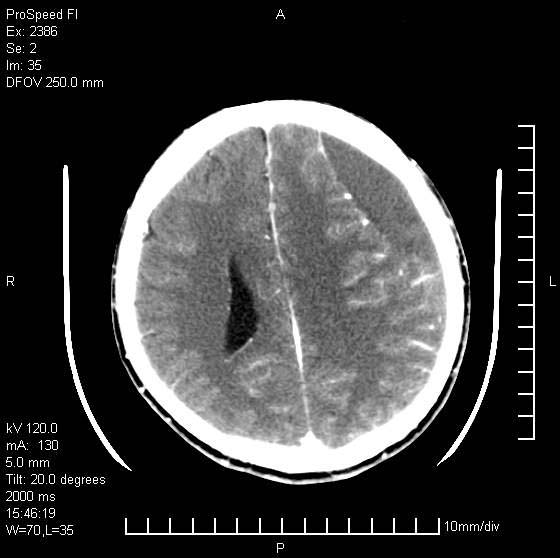

以下是引用天南地北在2007-9-19 18:43:00的发言:[br]典型慢性硬膜外血肿[br][br][本贴已被 天南地北 于 2007-9-19 18:44:11 修改过]

以下是引用曼一拍在2007-9-20 11:06:00的发言:[br]支持慢性硬膜下血肿.[br]慢性硬膜下积液:血肿有包膜,ct值稍高于脑脊液,增强可有染色。不典型者血肿可多呈梭形.是硬脑膜与蛛网膜之间的潜在腔隙内的血肿。[br]鉴别:[br]1\\硬膜外血肿:是颅脑外伤后脑膜或板障内血管破裂,血液在颅骨与硬膜之间积聚所致.通常是脑膜动脉破裂,也可因静脉窦破裂或颅骨的板障静脉出血,发生于外伤的着力部,常与颅骨骨折并存。脑膜动脉出血则急,若是板障静脉出血在则可有慢性。[br]2\\硬膜下积液:(硬膜下水瘤)[br]是由于蛛网膜破裂,脑脊液经蛛网膜破口进入硬膜下腔不能回流。或水肿阻塞而形成。[br]ct表现:颅骨内板下方新月形低密度区近似脑脊液密度;占位效应清,周围无脑水肿。[br]